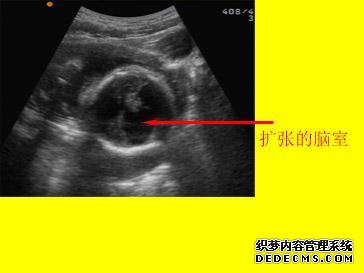

脑室脑积水的以下三个病理过程可能导致脑室扩大。1.脑积水2,脑室发育不良或周围组织3,脑周围组织破坏。

胎儿中枢神经系统超声解剖的妊娠中期和晚期以及侧脑室的常见畸形。